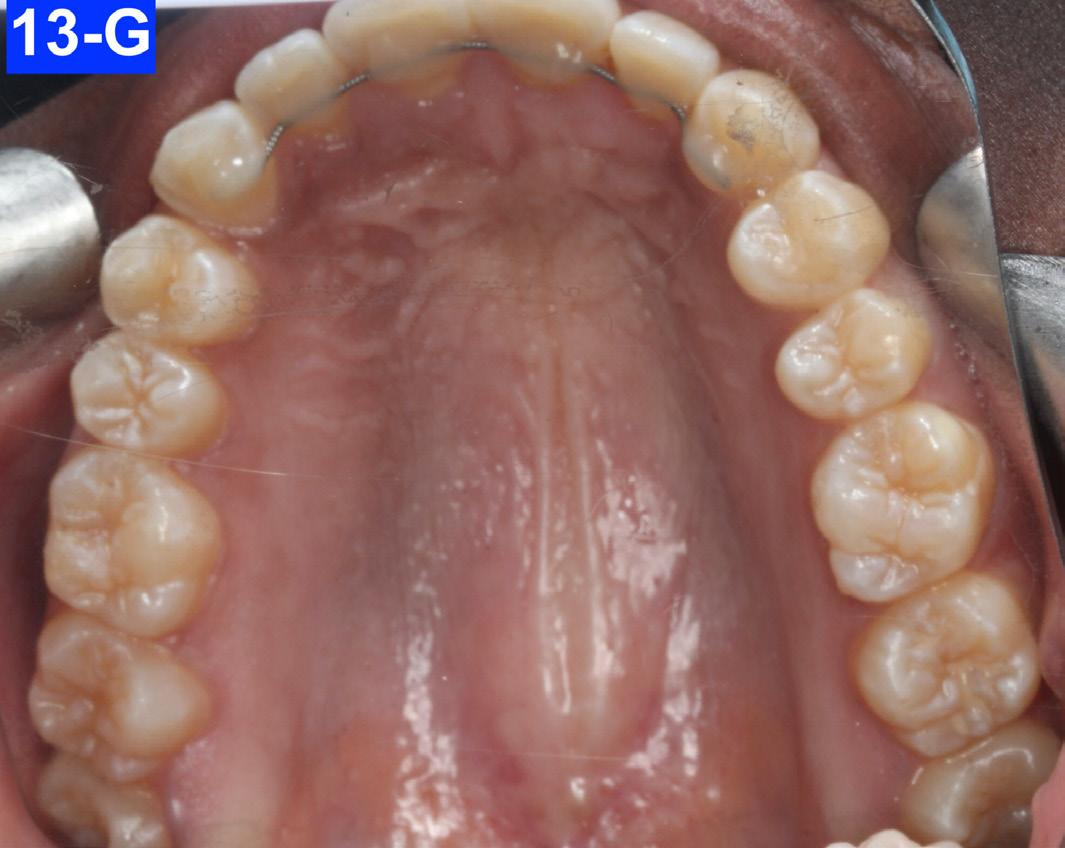

Figures 12-A to 12-M show the post-treatment images at the time of insertion of the retainers. We had an opportunity to evaluate the patient’s occlusion three years post-treatment. Compared to the initial post treatment evaluation, it was noted that the occlusion had settled into an even more stable position after three years.

Fig. 12-G: Post-treatment, MX occlusal view

Fig. 13-G: 3 years post-treatment, MX occlusal view